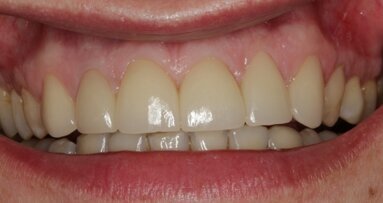

67-letnia pacjentka zgłosiła się do gabinetu stomatologicznego w celu konsultacji w sprawie leczenia implantologicznego. W wywiadzie zgłaszała pewne ...